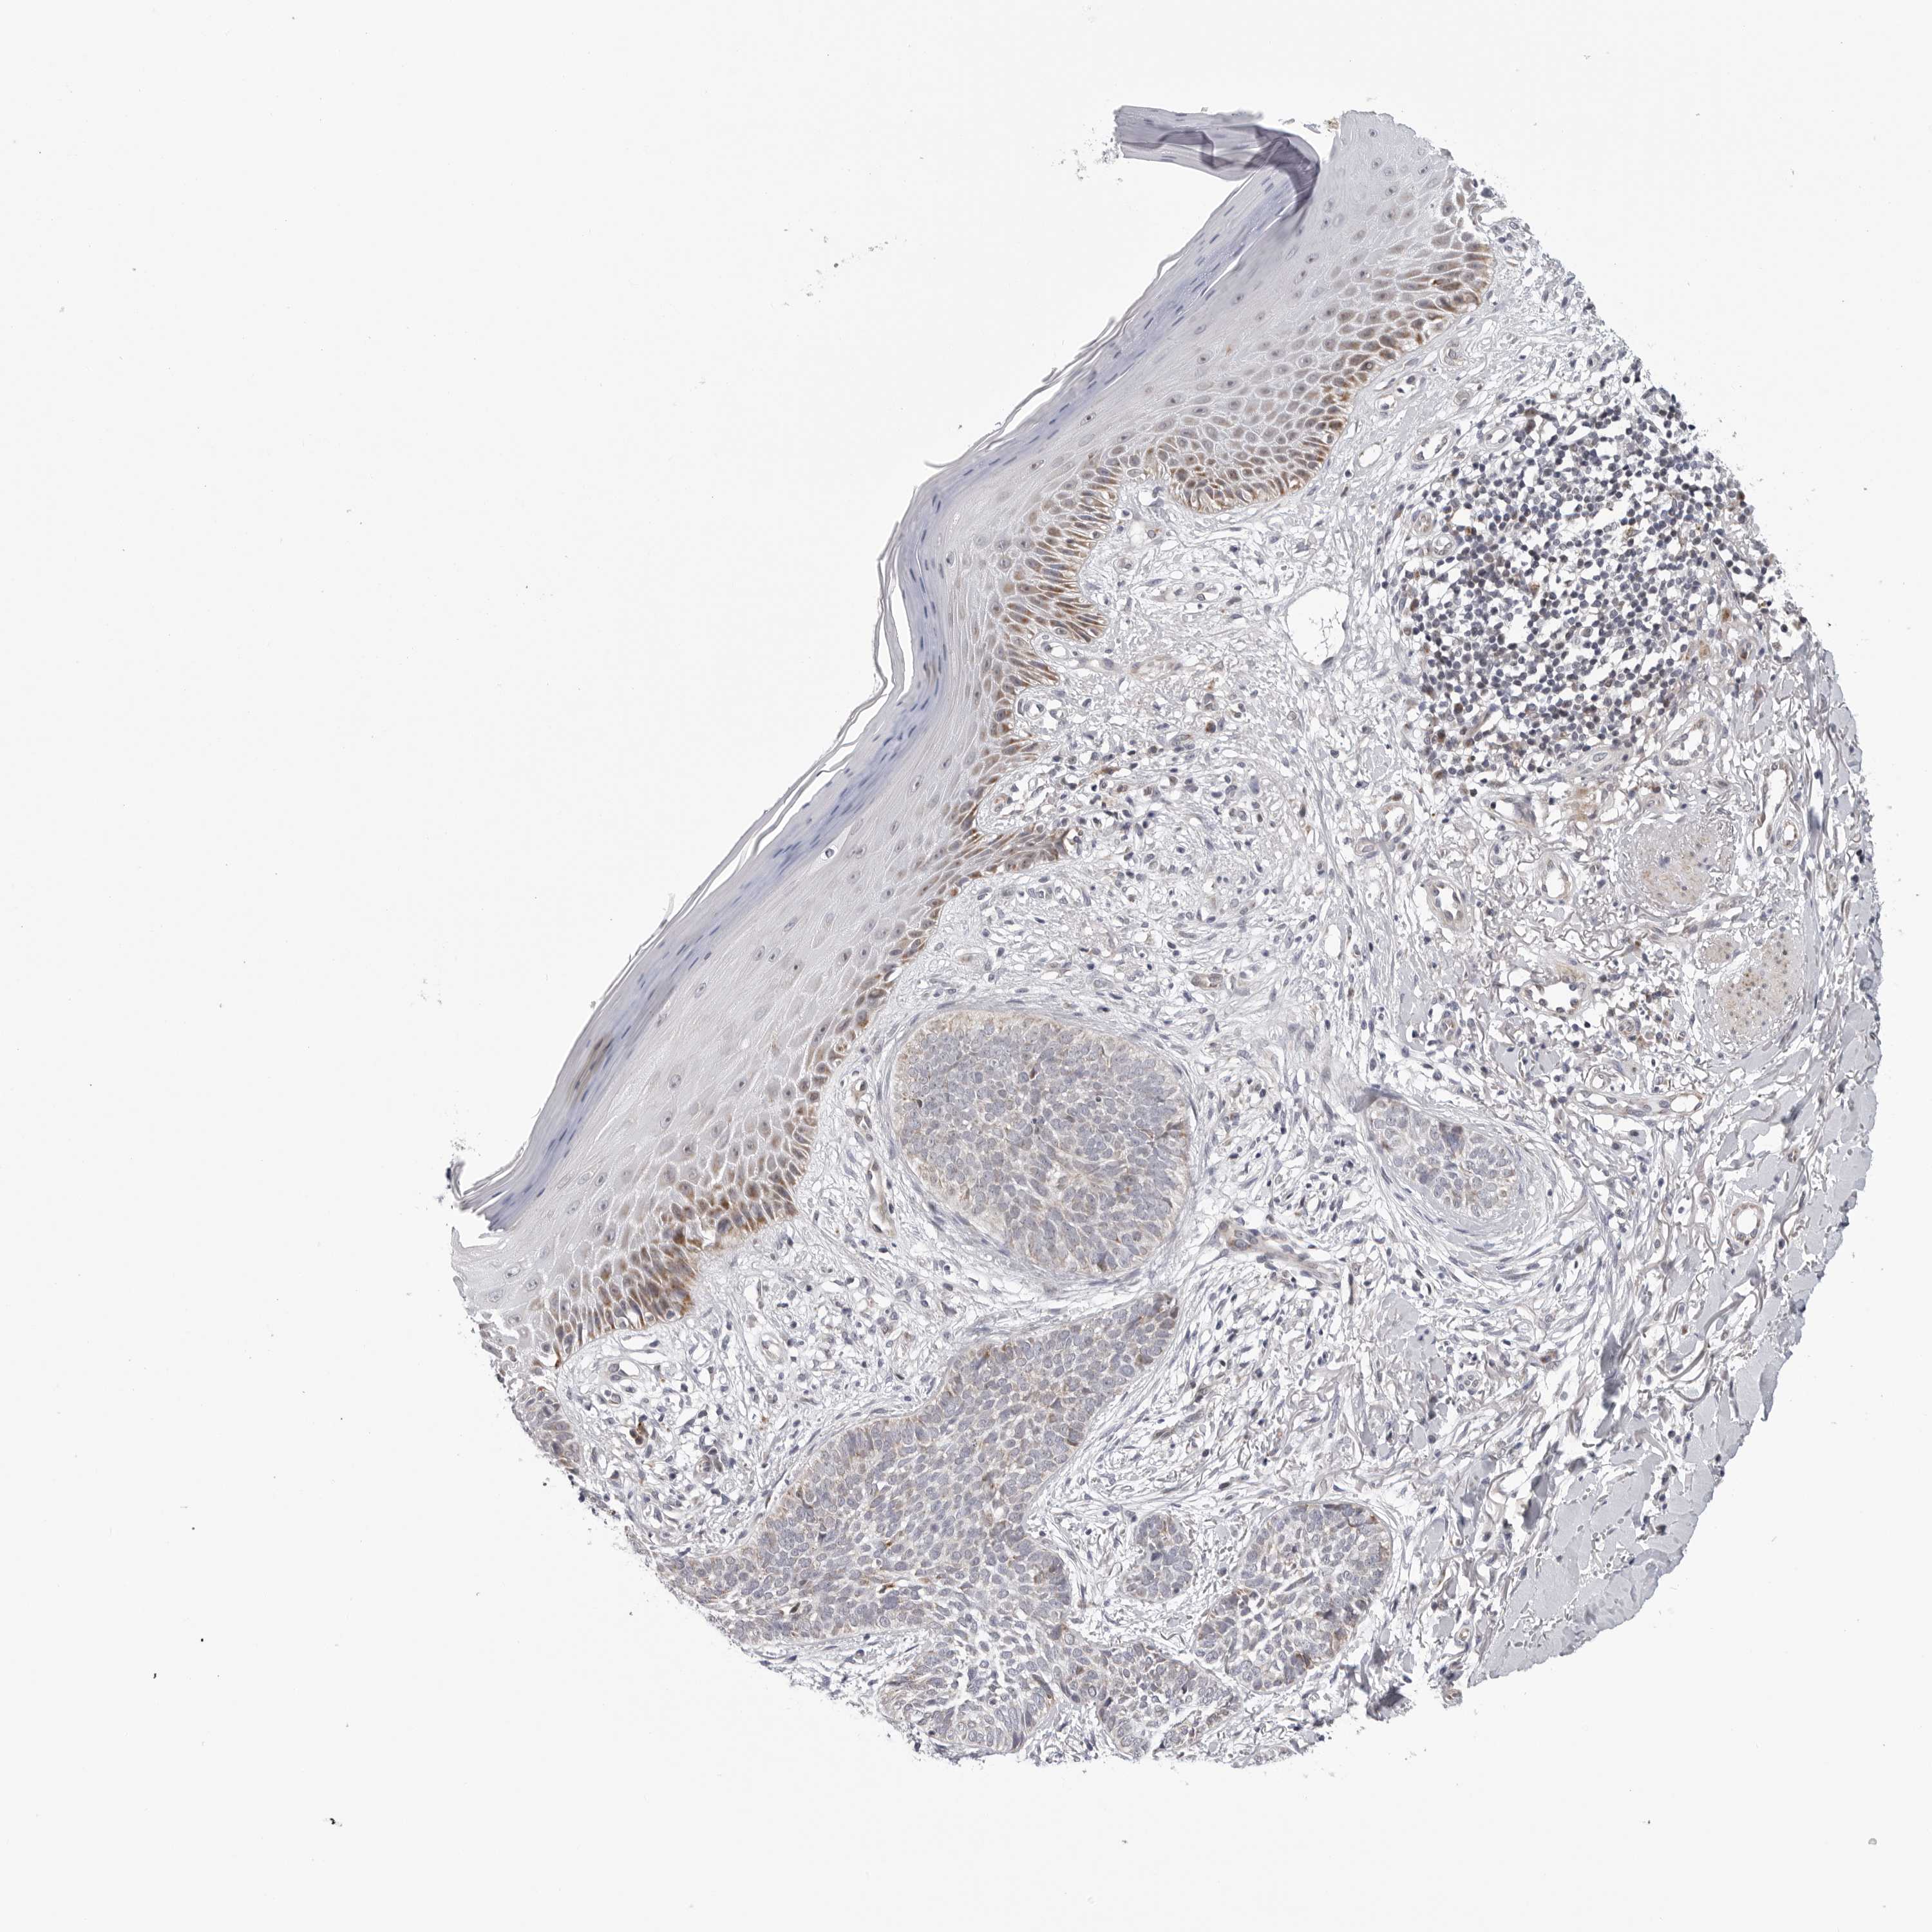

SKIN CANCER - Protein expressioni

A mouse-over function shows sample information and annotation data. Click on an image to view it in a full screen mode. Samples can be filtered based on level of antibody staining by selecting one or several of the following categories: high, medium, low and not detected. The assay and annotation is described here.

Each image is clickable and will lead to virtual microscopy that enables deeper exploration of all samples and also displays staining intensity scores, fraction scores and subcellular localization as well as patient and tissue information for each sample.

Antibody HPA027379

Squamous cell carcinoma, NOS